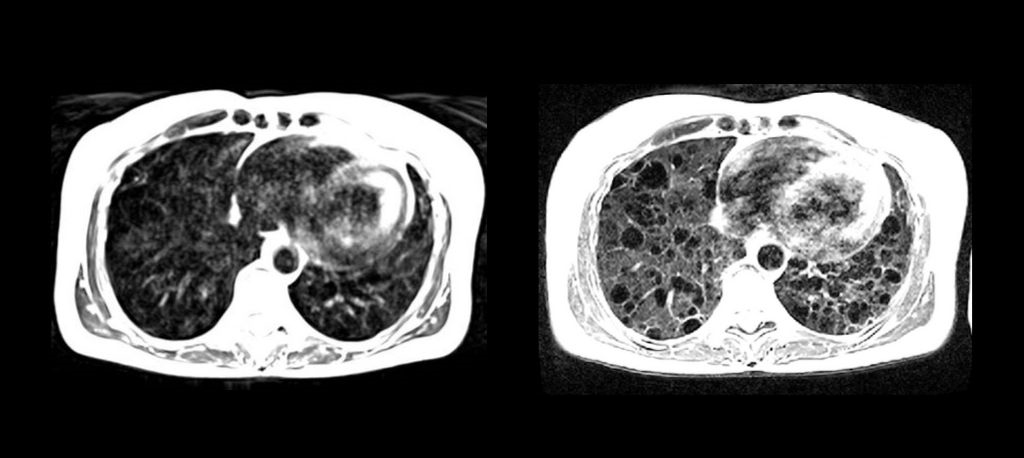

When compared with images obtained at 1.5T, researchers saw lung cysts and surrounding tissues in patients with lymphangioleiomyomatosis, or LAM, more clearly. In addition, researchers found that inhaled oxygen could increase the brightness of lung tissue more effectively using the lower magnetic field strength when compared to the higher field strength. These results show how useful low-field MRI can be in helping identify problems in the lungs.